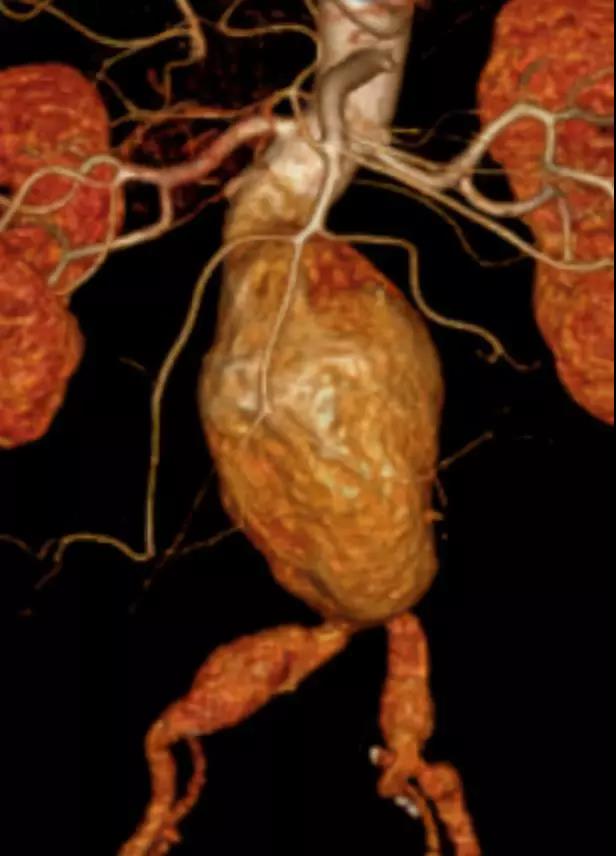

此次研究,纳入腹主动脉瘤的最大直径为85mm,平均直径为50.78mm;最短瘤颈长度为11mm,平均长度为31.34mm;最大肾下成角为74.6度,平均角度为32.48度。从动脉瘤最大直径变化来看,经过腹主动脉腔内治疗后,在出院前和术后6个月都有所减小。 在此次研究中,先健Yuranos™新一代腹主动脉覆膜支架系统临床试验初步展现了优秀的临床试验结果,其30天内MAE发生率低,安全性得以验证;而且由于该产品的柔顺性有较大提升,输送器直径减小,对于短瘤颈和角度大的病例是更好的选择。 入组病例展示: 病例一:男性,年龄69岁,既往高血压,糖尿病病史。术前腹主动脉瘤直径67.3mm,近端瘤颈长度23.2mm,近端锚定区直径21.2mm,肾下成角60.5度。 术中从右侧股动脉穿刺,选用先健型号为AB-2412-50-120的主体支架,支架近端定位于右肾动脉开口处,后释放打开裸支架,并向下释放主体短分支,左侧输送进入先健髂动脉延长支架IE-1416-100,并释放,保留左侧髂内动脉。接着释放主体长分支,右侧输送进入先健髂动脉延长支架IE-1424-80,并释放,保留右侧髂内动脉。 手术顺利,无内漏,持续时间1小时10分钟。术后CTA检查,支架形态良好,无内漏。详见下图: 术前影像 术中影像 出院前影像 术后6个月影像 术后1年影像 病例二:女性,年龄72岁,既往高血压,静脉曲张病史。术前腹主动脉瘤直径48.81mm,近端瘤颈长度16.15mm,近端锚定区直径18.43mm,肾下成角66度。 术中从右侧股动脉穿刺,选用先健型号为AB-2412-50-140的主体支架,支架近端定位于右肾动脉开口处,后释放打开裸支架,并向下释放主体短分支,左侧输送进入先健髂动脉延长支架IE-1414-120,并释放,保留左侧髂内动脉。接着释放主体长分支,右侧输送进入先健髂动脉延长支架IE-1414-80,并释放,保留右侧髂内动脉。